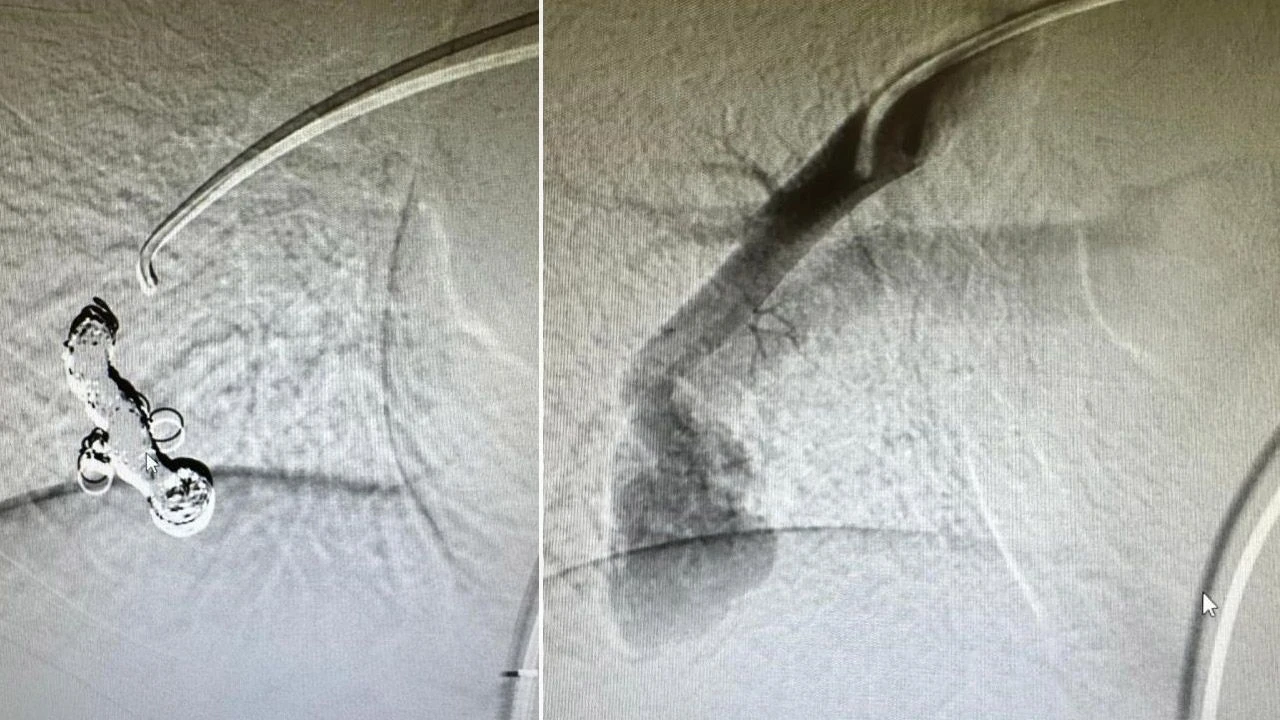

Çocuğun akciğerlerinde saptanılan yumak, endovasküler yolla (damar içerisinden) Samsun Eğitim ve Araştırma Hastanesi Girişimsel Radyoloji Uzmanı Doç. Dr. Hasan Gündoğdu ve Radyoloji Uzm. Dr. Öğr. Üyesi Mirsad Yalçınkaya tarafından tedavi edildi.

Tedavi ile ilgili bilgi veren Doç. Dr. Hasan Gündoğdu, "Böyle bir hastalığı hem saptamak hem de ilgili merkeze yönlendirmek gerçekten çok zor bir iştir. Dr. Fazıl Can hocamın hem hastalığı saptadı hem de ilgili merkeze yönlendirdi. Biz de girişimsel radyoloji ekibi olarak Dr. Mirsad hocamla birlikte hastamızın tedavisini en kısa zamanda gerçekleştirdik. Bizim açımızdan son derece güzel bir operasyon oldu. Bölgemizde ve hastanemizde ilk defa böyle bir operasyonu başarılı bir şekilde gerçekleştirdik. Çocuğumuzun bundan sonra diğer çocuklarla birlikte aynı şekilde oynayabilecek olması, semptomunun ortadan kalkması bizleri sevindirdi. Bu hastalarda eğer tedavi edilmezse ilerleyen yaşlarda kan oksijen değerinin düşük olmasıyla birlikte çocukluk çağından oynayamayacak, belirli aktiviteleri yerine getirilmeyecekti. Bu da çocukta ruhsal problemleri ortaya çıkarabilecekti. Ayrıca burada damar yumağının daha da büyümesi sonucu hastada akciğerde ciddi kanamalara sebebiyet verebilirdi. Daha büyük problemleri ortaya çıkarabilirdi” dedi.

Çocuk Göğüs Hastalıkları Uzmanı Fazılcan Zirek ise "Ahmet Utku, Çocuk Göğüs Hastalıklar Polikliniğe geçen ay başvurdu. Geldiğinde şikayeti parmaklarında ve dudaklarında olan morarmasıydı. Uzun süredir bu şikayeti varmış. Beraberinde ise halsizliği ve baş ağrısı varmış. Hastamızın muayenesinde el parmaklarındaki bombeleşmeyi gördük. Hem bu morar dediğimiz siyanoz durumu hem de parmaklardaki çomaklaşma durumu bizim açımızın oksijen seviyesinin düşmesini gösteriyor. Tetkiklerimizi yaptık. İlk muayenemizde satürasyonu 84 olarak gördük. Çocuk hastalarda 93 bekliyoruz. Öyle olunca bir dizi tetkiklerini yaptık. Tetkiklerini yaptığımızda normalde olmaması gereken damar bağlantısı gördük. Normalde atardamarla kan gittikten sonra temizlenir toplardamar ile tekrar vücuda geri döner. Bunları da kılcal dediğimiz filtre görevindeki damarlar yapar. Bizim hastamızda bu damar bağlantısında filtre yapı yoktu. Böyle olunca kan temizlenmeden, direk olarak vücuda gidiyordu. Bu da oksijen düşüklüğüne neden oluyordu. Tetkiklerimizi yaptık ve tanımızı koyduk. Girişimsel radyoloji ekibi ile birlikte müdahalesini yaptık. Bu hastalarda en sık müdahale yöntemi embolizasyon dediğimiz şantın kapatılması işlemidir. Bu hastalar çok nadir görülen hastalardır. Genellikle erişkin yaşta tanı koyulur ama çocuklarda da görebiliyoruz. Doğuştan olabiliyor. Tedavisini yaptık. Tedavi sonrasında satürasyonu düzeldi. Hastamızın şikayetleri de geriledi" diye konuştu.